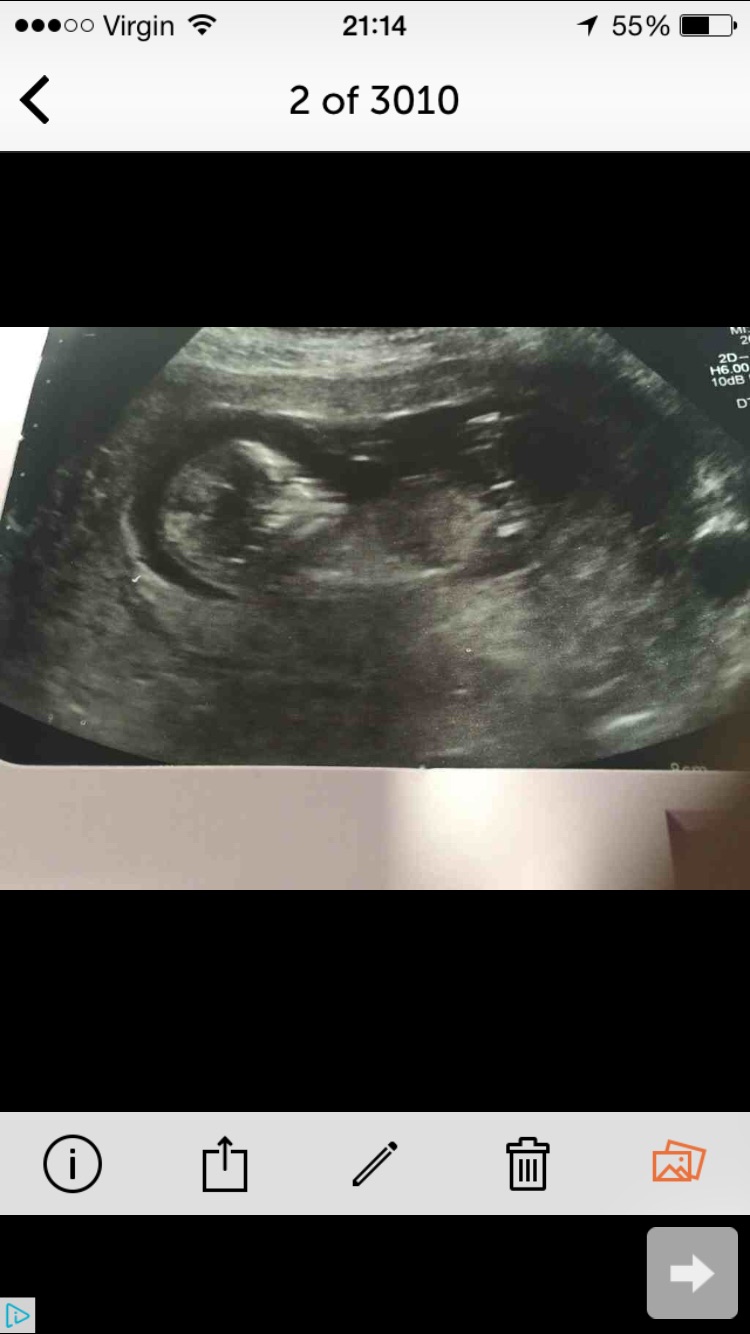

Unusual nub please please help!?! :)

I have what seems like a very unusual nub on this scan pic and none of the other sites seems to be able to guess - please can you try

It's definately not the textbook boy nub in fact I can't say I've seen one looking like this in any of the millions of pics I have seen online either

Desperately need support also if you can tell me how you interpreted it I would be so grateful

This was taken at 14+5 thanks so much xxx